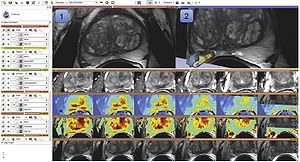

Automatic Classification of Prostate Cancer Gleason Scores from Multiparametric Magnetic Resonance Images

Publication: Proc Natl Acad Sci U S A. 2015 Nov 17;112(46):E6265-73. PMID: 26578786 | PDF Authors: Fehr D, Veeraraghavan H, Wibmer A, Gondo T, Matsumoto K, Vargas HA, Sala E, Hricak H, Deasy JO. Institution: Department of Medical Physics, Memorial Sloan Kettering Cancer Center, New York, NY, USA. Background/Purpose: Noninvasive, radiological image-based detection and stratification of Gleason patterns can impact clinical outcomes, treatment selection, and the determination of disease status at diagnosis without subjecting patients to surgical biopsies. We present machine learning-based automatic classification of prostate cancer aggressiveness by combining apparent diffusion coefficient (ADC) and T2-weighted (T2-w) MRI-based texture features. Our approach achieved reasonably accurate classification of Gleason scores (GS) [Formula: see text] vs. [Formula: see text] and [Formula: see text] vs. [Formula: see text] despite the presence of highly unbalanced samples by using two different sample augmentation techniques followed by feature selection-based classification. Our method distinguished between GS [Formula: see text] and [Formula: see text] cancers with 93% accuracy for cancers occurring in both peripheral (PZ) and transition (TZ) zones and 92% for cancers occurring in the PZ alone. Our approach distinguished the GS [Formula: see text] from GS [Formula: see text] with 92% accuracy for cancers occurring in both the PZ and TZ and with 93% for cancers occurring in the PZ alone. In comparison, a classifier using only the ADC mean achieved a top accuracy of 58% for distinguishing GS [Formula: see text] vs. GS [Formula: see text] for cancers occurring in PZ and TZ and 63% for cancers occurring in PZ alone. The same classifier achieved an accuracy of 59% for distinguishing GS [Formula: see text] from GS [Formula: see text] occurring in the PZ and TZ and 60% for cancers occurring in PZ alone. Separate analysis of the cancers occurring in TZ alone was not performed owing to the limited number of samples. Our results suggest that texture features derived from ADC and T2-w MRI together with sample augmentation can help to obtain reasonably accurate classification of Gleason patterns. Funding:

Example of (A) a GS 6(3+3) tumor and (B) a GS 9(4+5) tumor. The top row shows the ADC image with the computed energy and entropy values overlaid on the tumor. The bottom row shows the T2-w MR image with the computed energy and entropy values overlaid on the same tumor on the corresponding slice. The texture features were computed per voxel by using a 5×5×5 patch centered at each voxel. Tumors and normal structures were identified and volumetrically segmented on both the T2-w and ADC MR images using 3D Slicer. |